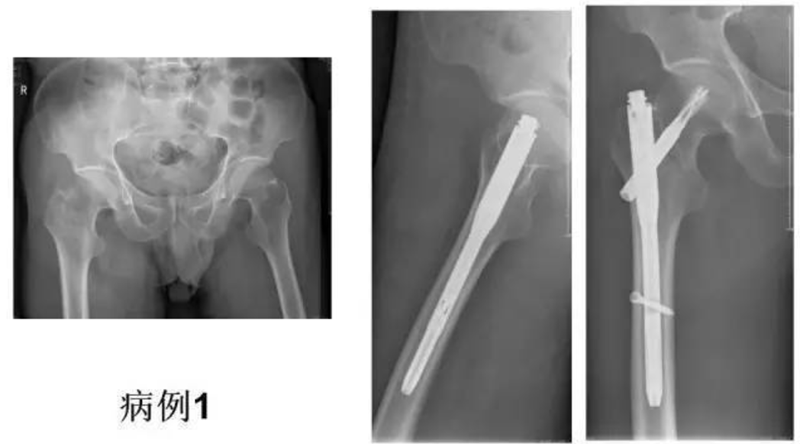

图1 典型病例xx男71岁粗隆间骨折3天Evans-Jensen分型V型4骨折片段,缺乏内侧和外侧的支持

Xxx,男,71岁,右股粗隆间骨折3天,Evans-Jensen分型V型4分骨折块骨折;2020.2.28手术。

图18、图19